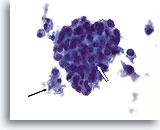

Atypische proliferatieve ductale laesie, Borst FNA, Diff-Quick gekleurde uitstrijk.

De ductale cellen zijn in drie dimensies opgestapeld. Er is geen duidelijke populatie myoepitheliale cellen en linksonder is er slechts focaal mogelijk gedeelde polariteit van aangrenzende ductale cellen.

60X

Atypische proliferatieve ductale laesie, Borst FNA, Diff-Quick gekleurde uitstrijk.

De ductale cellen zijn in drie dimensies opgestapeld. Er is geen duidelijke populatie myoepitheliale cellen en linksonder is er slechts focaal mogelijk gedeelde polariteit van aangrenzende ductale cellen.

60X